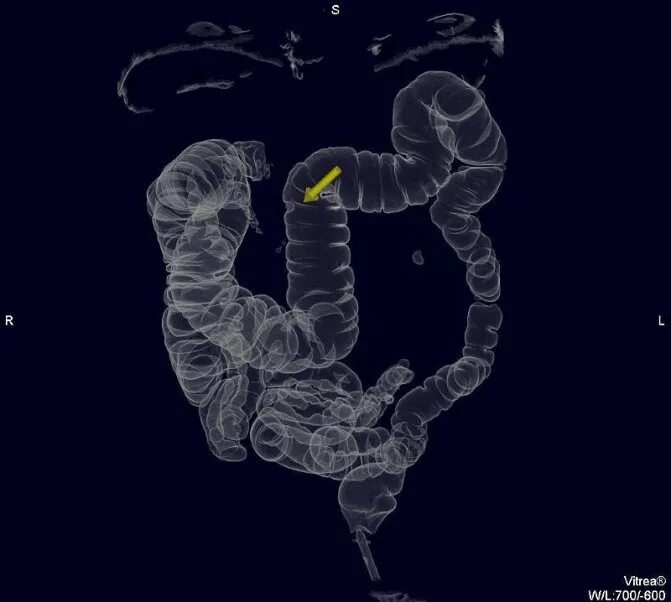

Обследование кт кишечника